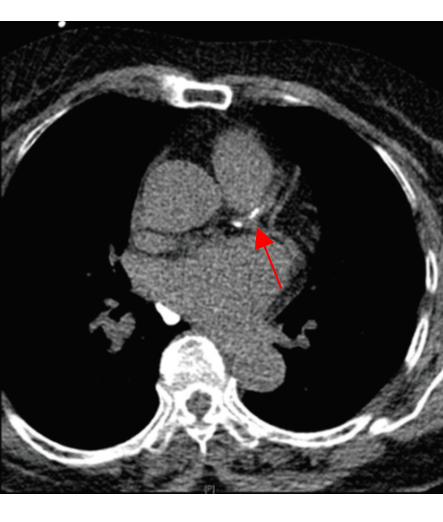

관상동맥질환을 일으키는 주된 원인은 동맥경화증이다. 인체의 상수도에 해당하는 동맥이 각종 원인에 의해 통로가 좁아져 혈액의 흐름에 장애가 발생하는 상태라고 할 수 있다. 협심증과 심근경색이 대표적인 질환이다. 관상동맥질환의 위험도를 볼 수 있는 가장 간편한 방법은 관상동맥 칼슘(석회화) 수치를 측정하는 것이다. 동맥경화가 발생, 진행하는 과정에서 칼슘이 생성 혹은 침착되기 때문이다. 관상동맥 칼슘은 컴퓨터단층촬영(CT)으로 발견 및 정량화가 가능하다. 1회 측정할 때 방사선량은 0.9~1.1밀리시버트(mSv)다. 방사선수치가 높은 만큼 관상동맥 칼슘의 유병률이 매우 낮은 40세 미만의 남자와 50세 미만의 여자에게는 일반적으로 관상동맥 칼슘 측정을 위한 CT 촬영은 권하지 않는다.

관상동맥 칼슘 수치가 400 이상인 경우에는 단일광자단층촬영(SPECT) 등 심근관류영상 검사를 고려할 수 있다. 일부 연구에서는 관상동맥 칼슘수치가 400 이상인 환자들 중 많게는 3분의 1이 심근 허혈이 있었다고 보고되고 있다. 환자의 연령, 성별, 활동 능력, 병원의 검사 정도 관리, 담당 의사의 선호도에 따라 심근관류영상 대신 운동부하 검사나 부하 심초음파 검사를 시행하는 것도 고려할 수 있다. 조영제를 사용하는 관상동맥 CT 혈관조영술을 촬영하는 것도 고려할 수는 있으나 석회화가 심한 경우 정확한 평가가 어려울 수 있으며 병변의 기능적 유의성에 대한 정보를 얻기 어려운 단점이 있다. 400 미만이라 할지라도 칼슘의 분포나 환자의 동반 질환 혹은 위험인자에 따라 검사를 진행하는 경우도 많이 있다. 이렇게 시행한 추가검사에서 이상 소견이 발견된다면 순환기내과 혹은 심장내과 전문 의사를 찾아야 한다.